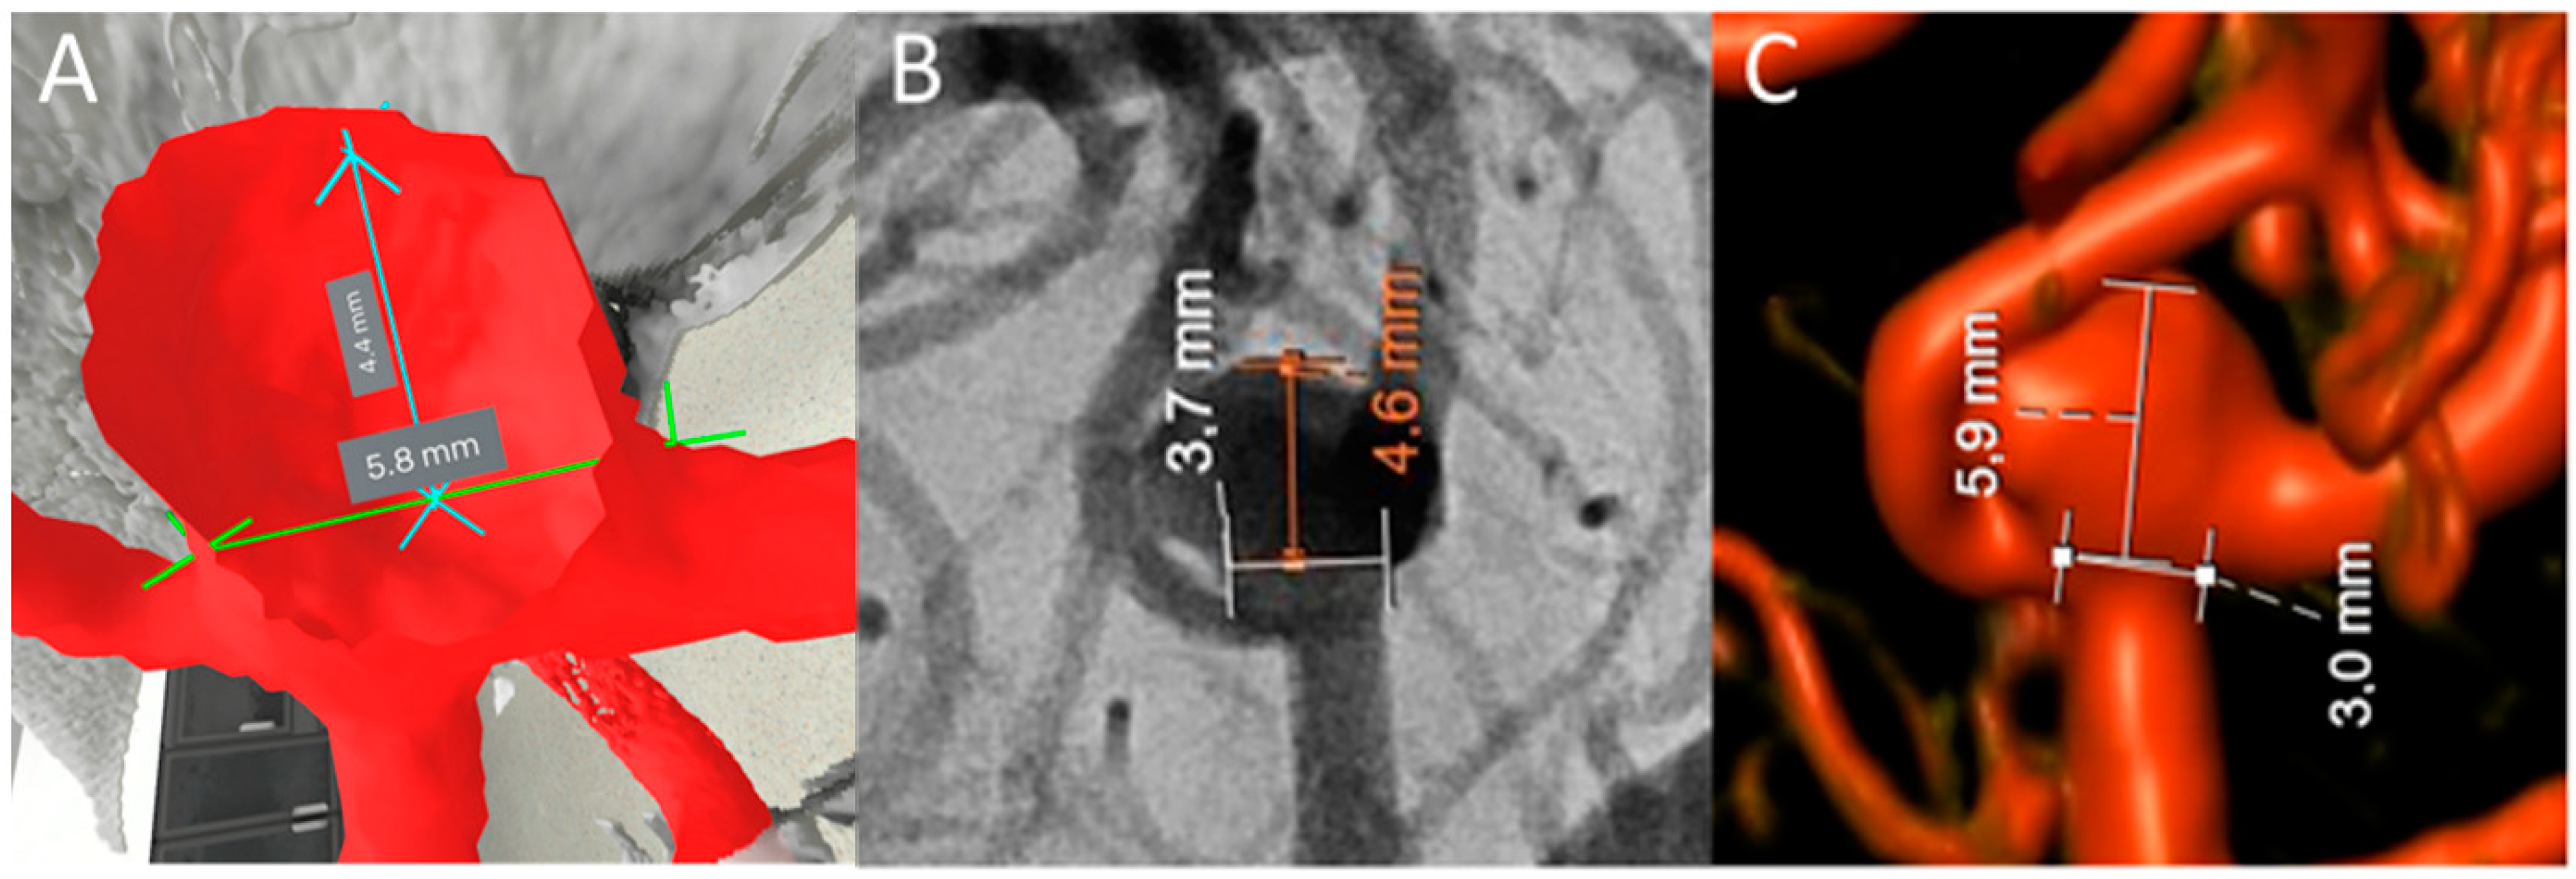

Figure 1. Comparison of 2D DSA, 3D DSA, and 3D VR measurements. (A) Measurement of neck diameter and maximum perpendicular aneurysm height using 3D VR. (B) Measurement of neck diameter and maximum perpendicular height using 2D DSA. (C) Measurement of neck diameter and maximum perpendicular aneurysm height using 3D DSA reconstructions.